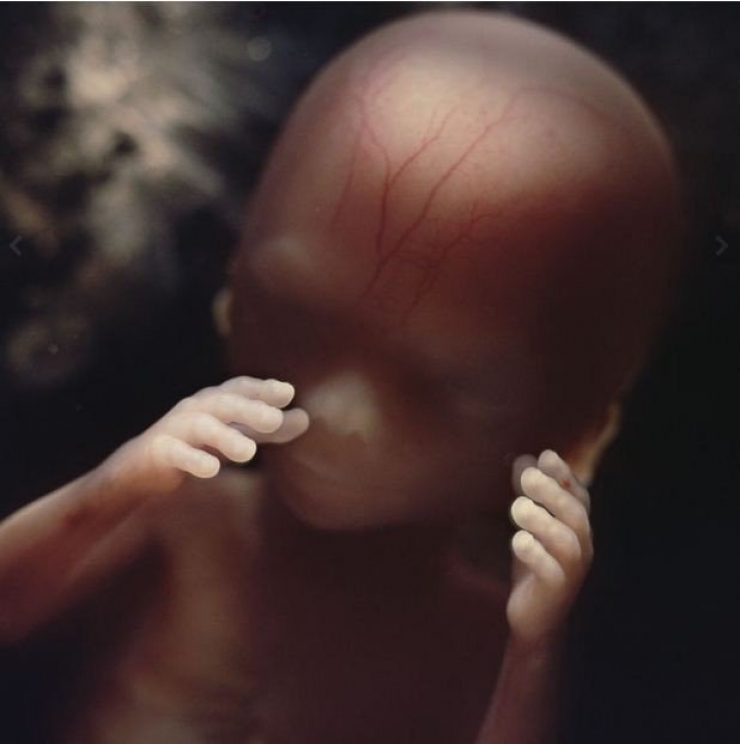

13: Au bout de 8 semaines de développement

14: Au bout de 10 semaines... Les paupières des yeux commencent à se former...

15: Au bout de 10 semaines également, l'embryon peut déjà toucher et sentir de ses mains l'environnement